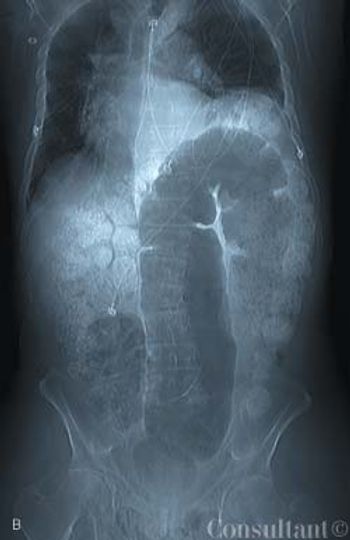

An HIV-positive 38-year-old man with a history of injection drug use presented to the emergency department with abdominal and back pain that worsened with motion. He denied fever and vomiting. During the past 2 months, the patient had been treated for a urinary tract infection (UTI) 4 times and evaluated for a renal calculus, which had been ruled out. He was currently receiving ciprofloxacin, ibuprofen, and HAART.